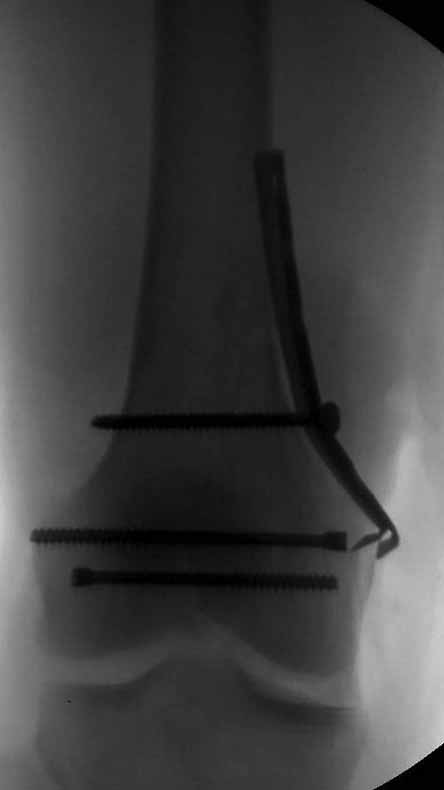

Ответ на эту часть Вашего поста – вложенный файл. Больная оперирована неделю назад по поводу открытого перелома дистального эпиметафиза бедренной кости. После операции она идёт в рентгенкабинет для выполнения послеоперационной контрольной рентгенографии, представленной на слайдах 10 и 11. Узнав, почему её фотографируют, просила передать Вам, Антон, привет.

В приложении пример недавней операции, C3, открытая репозиция, фиксация мыщелков спицами и винтами, ретроградный синтез большеберцовым гвоздем 10,5 мм диаметром, винты 5 мм.

Позволю себе напомнить коллегам ещё раз, что являюсь сторонником антеградного остеосинтеза при переломах дистального эпиметафиза бедренной кости. Такая приверженность основана не на преимуществах внесуставного введения стержня или большем проценте положительных результатов. Она основана на возможности обеспечить блокирование на минимальном расстоянии от суставной поверхности в нескомпрометированной кости и, таким образом стабилизировать максимально низкие переломы. В приведенном Вами случае самый дистальный из блокирующих винтов проведен на расстоянии более 2 см от конца стержня. Из-за того, что к стержню присоединяется кондуктор, на стержне теряется 1-1,5 см его длины, где можно было разместить отверстия для блокирования. И что более важно, вместе с потерянной для этой цели длиной стержня утрачивается для размещения блокировочных винтов, пожалуй, самая ценная часть дистального эпиметафиза бедренной кости. Проблемы дистального блокирования в разных плоскостях, локализации точки ввода стержня при антеградном остеосинтезе – это всё решаемые технические проблемы. Но антеградный остеосинтез низких дистальных переломов бедра при адекватном блокировании в нескомпрометированной кости обеспечивает решение стратегической задачи – стабильный остеосинтез и возможность нагрузки.